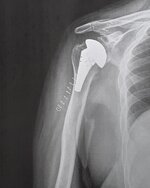

Second best is just a straight forward replacement! (see below)

562.jpg

Third best is a "reverse replacement". Socket on the humerus, ball on the shoulder.